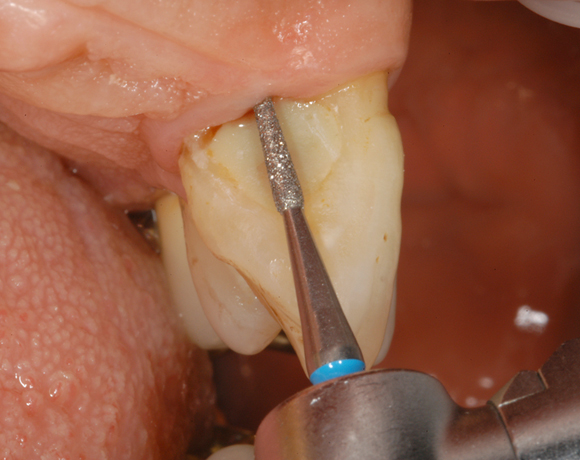

(Diamant- und Hartmetall-Instrumente Periodont Set) Zwei unterschiedliche Formen in zwei unterschiedlichen Schaftlängen, jeweils in Hartmetall und Diamant, erlauben die individuelle Behandlung der Wurzeloberfläche.

Das Periodont Set im Einsatz.